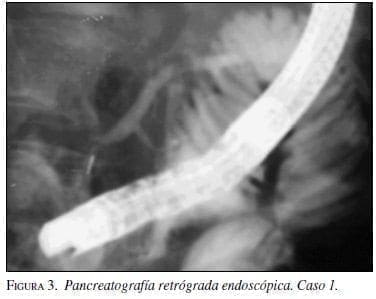

Luego de la intervención se trasladó a la unidad de cuidado intensivo (UCI), donde permaneció 36 días, durante los cuales se realizaron varios lavados quirúrgicos, además de esplenectomía por encontrar el bazo isquémico. Dieciocho días después de la pancreatectomía se desarrolló una fístula pancreática externa de alto flujo con drenajes promedio de 350 ml/día y titulación de amilasa en 639.000 U/L. Se inició manejo conservador con nutrición enteral a yeyuno y octreótido x 100 µg subcutáneos cada ocho horas sin lograr mejoría, por lo que diez días después se realizó CPRE, pero no se pudo visualizar el escape (figura 3).